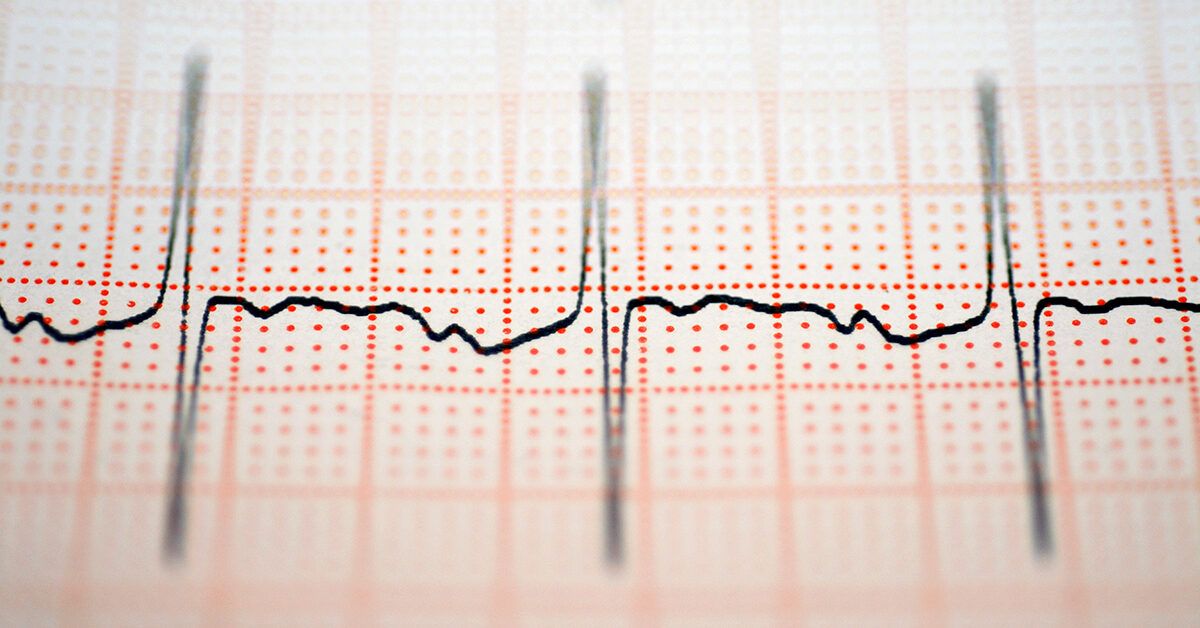

Heart Rate Variability (HRV) is an innovative health metric that tracks the subtle differences in the timing between your heartbeats. Unlike your heart rate, which counts the beats per minute, HRV measures the variation in intervals between each beat, offering a deeper look into your body's autonomic nervous system.

For example, even if your heart beats 60 times per minute, the time between each beat isn’t always exactly one second; some beats occur slightly earlier or later. This variability is a sign of your heart's adaptability and resilience.

The most precise HRV measurement comes from an electrocardiogram (EKG), which records the electrical activity of your heart and shows the intervals between beats, known as R-R intervals. Typically, a heart rhythm monitor worn for 5 minutes up to 24 hours can establish your baseline HRV.